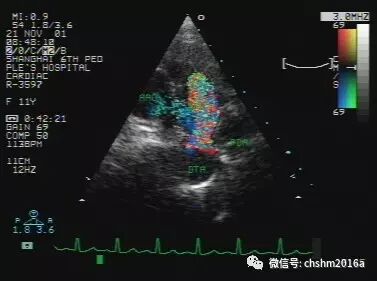

3.彩色多普勒血流显像

于胸骨旁大动脉短轴,分流束呈现以红色为主的五彩血流,起自降主动脉,经动脉导管进入肺动脉,沿主肺动脉外侧上升。

彩超伪像是什么先天性心脏病超声诊断(超声梦影像医生集团 CCM)_https://www.jmylbn.com_新闻资讯_第12张

图2.3.10   动脉导管未闭分流束由胸主动脉进入肺动脉

DTA:降主动脉胸段   PDA:动脉导管未闭